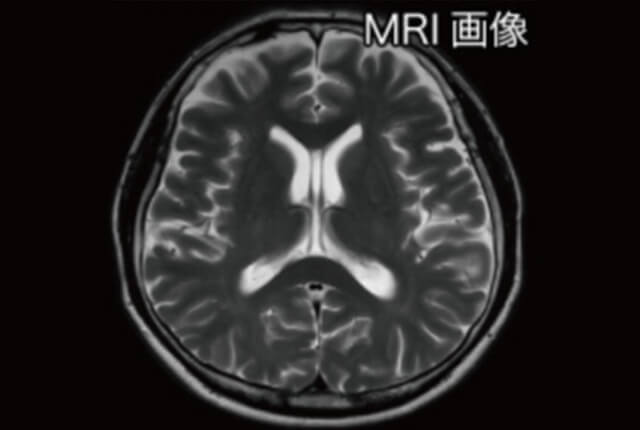

MRI検査(Magnetic Resonance Imaging)は、強力な磁場と電波を組み合わせて、体内の詳細な画像を取得し、その画像から異常を発見します。放射線を使わないため、被爆の心配はありません。この検査では脳梗塞や脳出血、脳腫瘍、動脈瘤などの病気を早期発見できます。検査時間はおおよそ20分程度です。